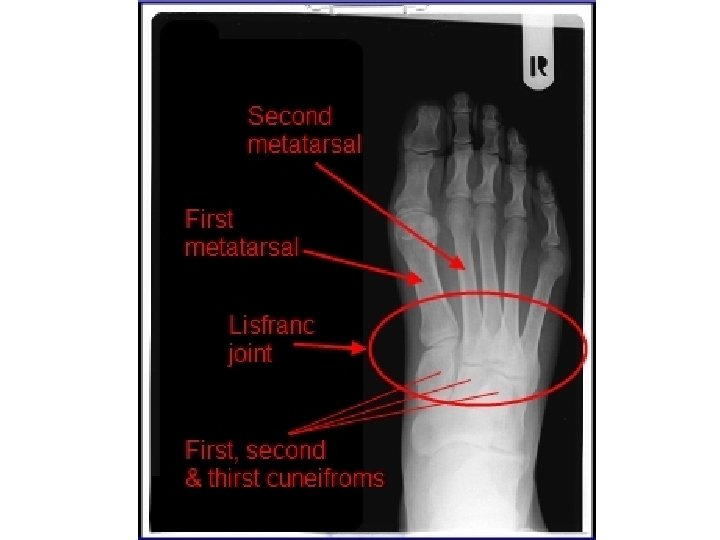

Lisfranc Joints The Lisfranc joints are between the first metatarsal, second metatarsal, medial cuneiform and intermediate cuneiform.

Lisfranc Joint Complex • To lessen ambiguity, some investigators have suggested that the term “Lisfranc joint complex” should be used to refer to tarsometatarsal articulations and that the term “Lisfranc joint” should be applied to medial articulation involving the first and second metatarsals with the medial (first) and middle (second) cuneiforms. • Myerson M. The diagnosis and treatment of injuries to the Lisfranc joint complex. Orthop Clin North Am. 1989; 20: 655– 64.

Lisfranc Injury • The Lisfranc joint complex includes the bones and ligaments that connect the midfoot and forefoot.